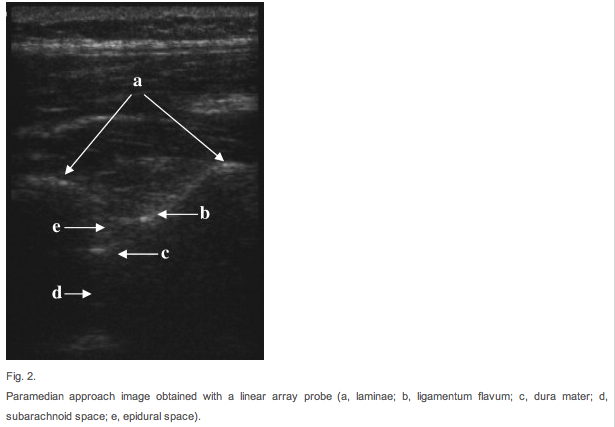

—Linear array probe for thin and pediatric patients

7. Rotate probe to long axis.

8. Center the interspinous process. Mark it.

9. Intersection of lines (sagittal and transverse) is site of needle entry

10. Align proposed needle insertion with the visualized interspinous space.

11. Measure depth required to penetrate subarachnoid space.